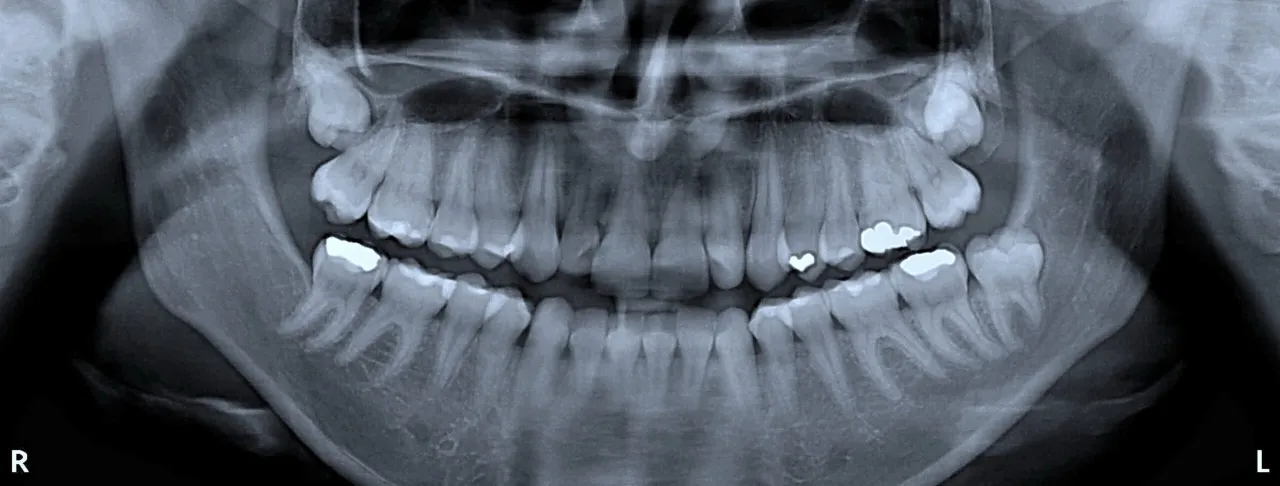

- Diagnostyka obrazowa (RTG): Zdjęcie rentgenowskie jest niemal zawsze konieczne przed ekstrakcją. Zdjęcie punktowe, obejmujące jeden ząb, to koszt około 50 zł. Jeśli konieczne jest zdjęcie pantomograficzne (panorama), które pokazuje wszystkie zęby i struktury szczęki, wydatek ten wyniesie od 100 zł do 150 zł. Przed usunięciem ósemek często wymagane jest nawet badanie CBCT (tomografia stożkowa), które jest droższe.